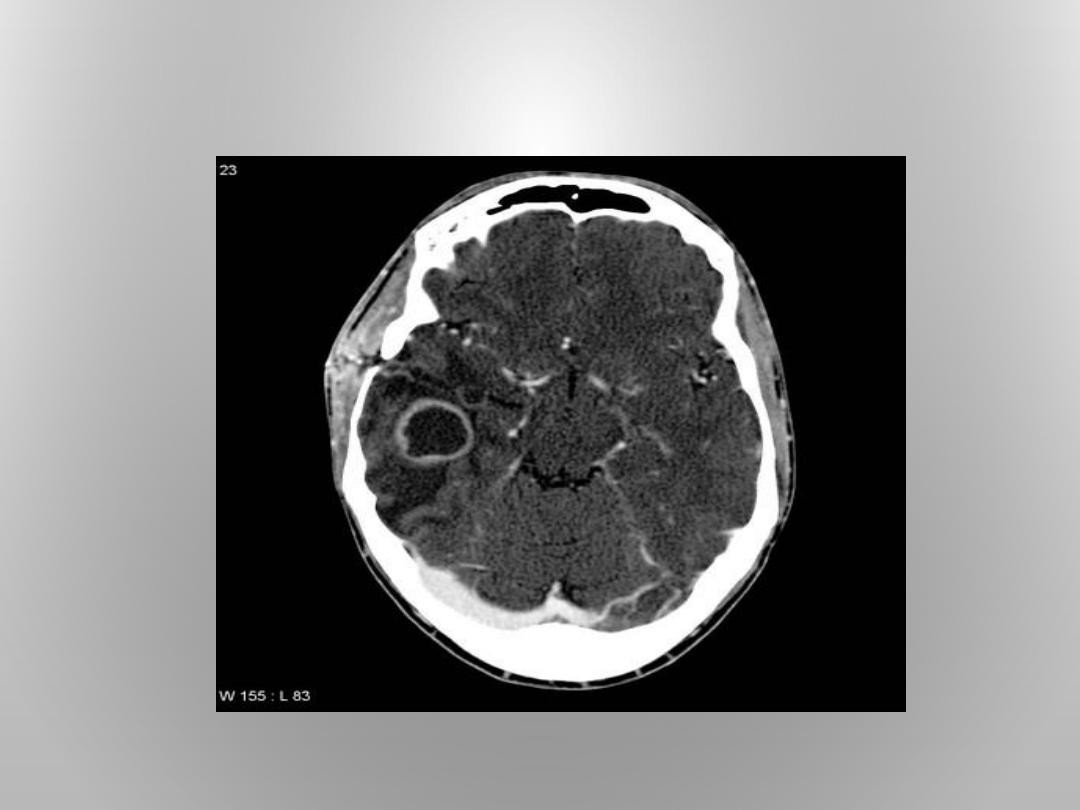

4. BRAIN ABSCESS:

A. TEMPORAL LOBE ABSCESS.

B. CEREBELLAR ABSCESS.

• 4-BRAIN ABSCESS : IT OCCURS IN THE TEMPORAL LOBE AND CEREBELLUM .

MORTALITY RATE IS 6%,THE SPREAD OF INFECTION THROUGH OSTIETIC

TEGMEN TYMPANI AND LATERAL SINUS

• THROMBOSIS.50% OF BRAIN ABSCESS IS OTOGENIC

* BRAIN ABSCESS (ASPIRATION,EXCISION).